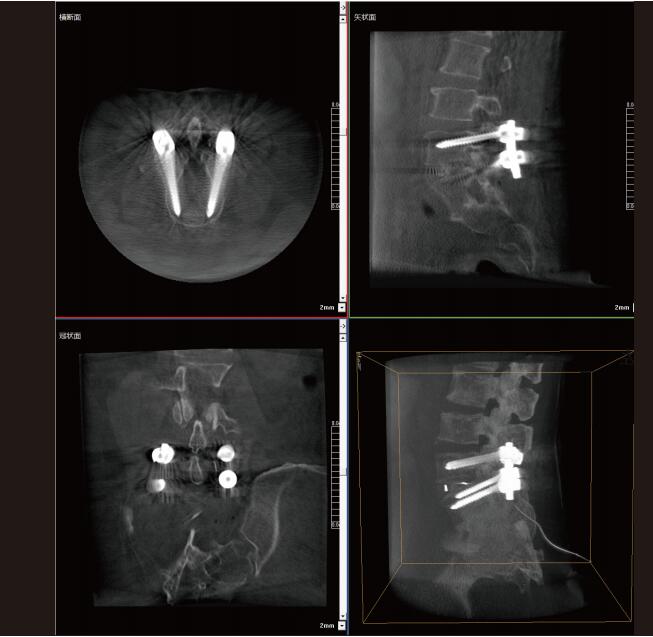

普愛醫(yī)療大功率移動式三維C形臂能夠在手術(shù)室內(nèi)提供高清的骨科二維及三維影像。通過掃描,在術(shù)中快速生成骨骼的三維立體成像,并提供橫斷面、矢狀面、冠狀面的類CT視圖,幫助醫(yī)師更精準(zhǔn)的診斷病灶、規(guī)劃手術(shù)治療方案。

大視野三維成像范圍

普愛醫(yī)療大功率移動式三維C形臂配置了30cm×30cm大尺寸動態(tài)平板探測器。一次掃描可呈現(xiàn)更多組織信息,可以覆蓋:

全段頸椎

全段腰椎

七節(jié)胸椎

雙側(cè)骶髂關(guān)節(jié)

股骨頭及單側(cè)盆骨